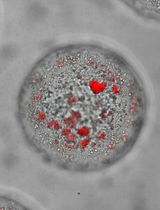

The binding protocols described here couple the specificity of BRET with the sensitivity and inherent cell-surface localization of the HiBiT/LgBiT reporter for quantification of binding interactions with selective GPCRs on the surface of living cells (Figure 1). They include four principal types of assays using β2-AR ligand binding as an example. Two of these assays utilize increasing concentrations of a fluorescent Tracer to measure its binding characteristics in equilibrium and real-time. The other two assays employ increasing concentrations of an unmodified test compound to derive its binding properties through the competition with a fixed concentration of a fluorescent Tracer. These competition analyses can be performed under equilibrium or in a kinetic format, which take advantage of a method reported by Motulsky and Mahan (1984).

Figure 1. Monitoring cell surface ligand engagement with selective HiBiT-tagged GPCRs via BRET. BRET assay utilizing fluorescent Tracers in a competitive binding format to quantify dynamic cell-surface interactions between ligands and their cognate HiBiT-tagged GPCRs. This approach benefits from high specificity as signal is generated only when the fluorescent Tracer and tagged GPCR are in close proximity.